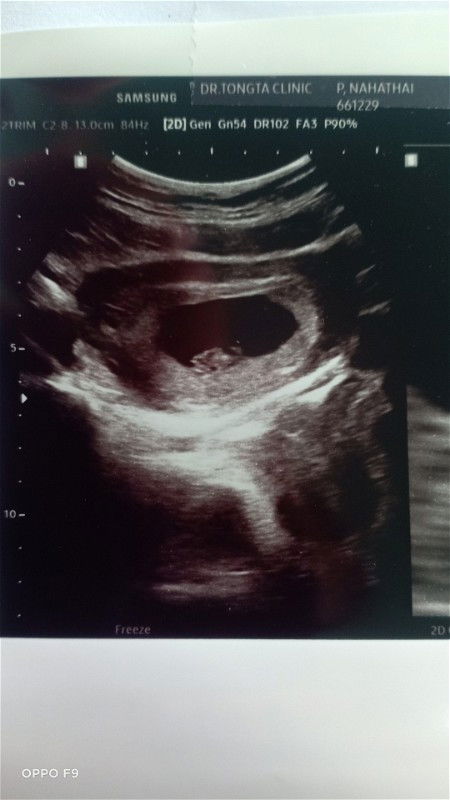

ไม่แน่ใจว่าคิดไปเอง มองเห็น2ถุง ตอนอัลตราซาวว์ 7+6วีค หมอไม่ได้บอก2ถุง เห็นถุงเห็นตัวอ่อน ก็ซูมดูหัวใจ เห็นหัวใจเต้น ตอนอยู่คลีนิคไม่ได้สังเกตุค่ะ สังเกตุในภาพทีหลัง แบบนี้มีโอกาสมั้ยค่ะ#ขอบคุณล่วงหน้านะคะ

มีโอกาสแฝดไหมค่ะ